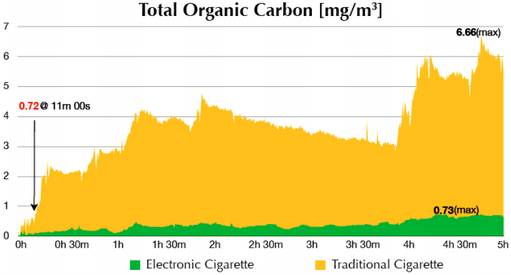

Результаты свидетельствуют, что содержание органического углерода, аналогичное таковому в курительной комнате после 11 минут, в комнатах, где парили, было зафиксировано только через 4.5 часа: